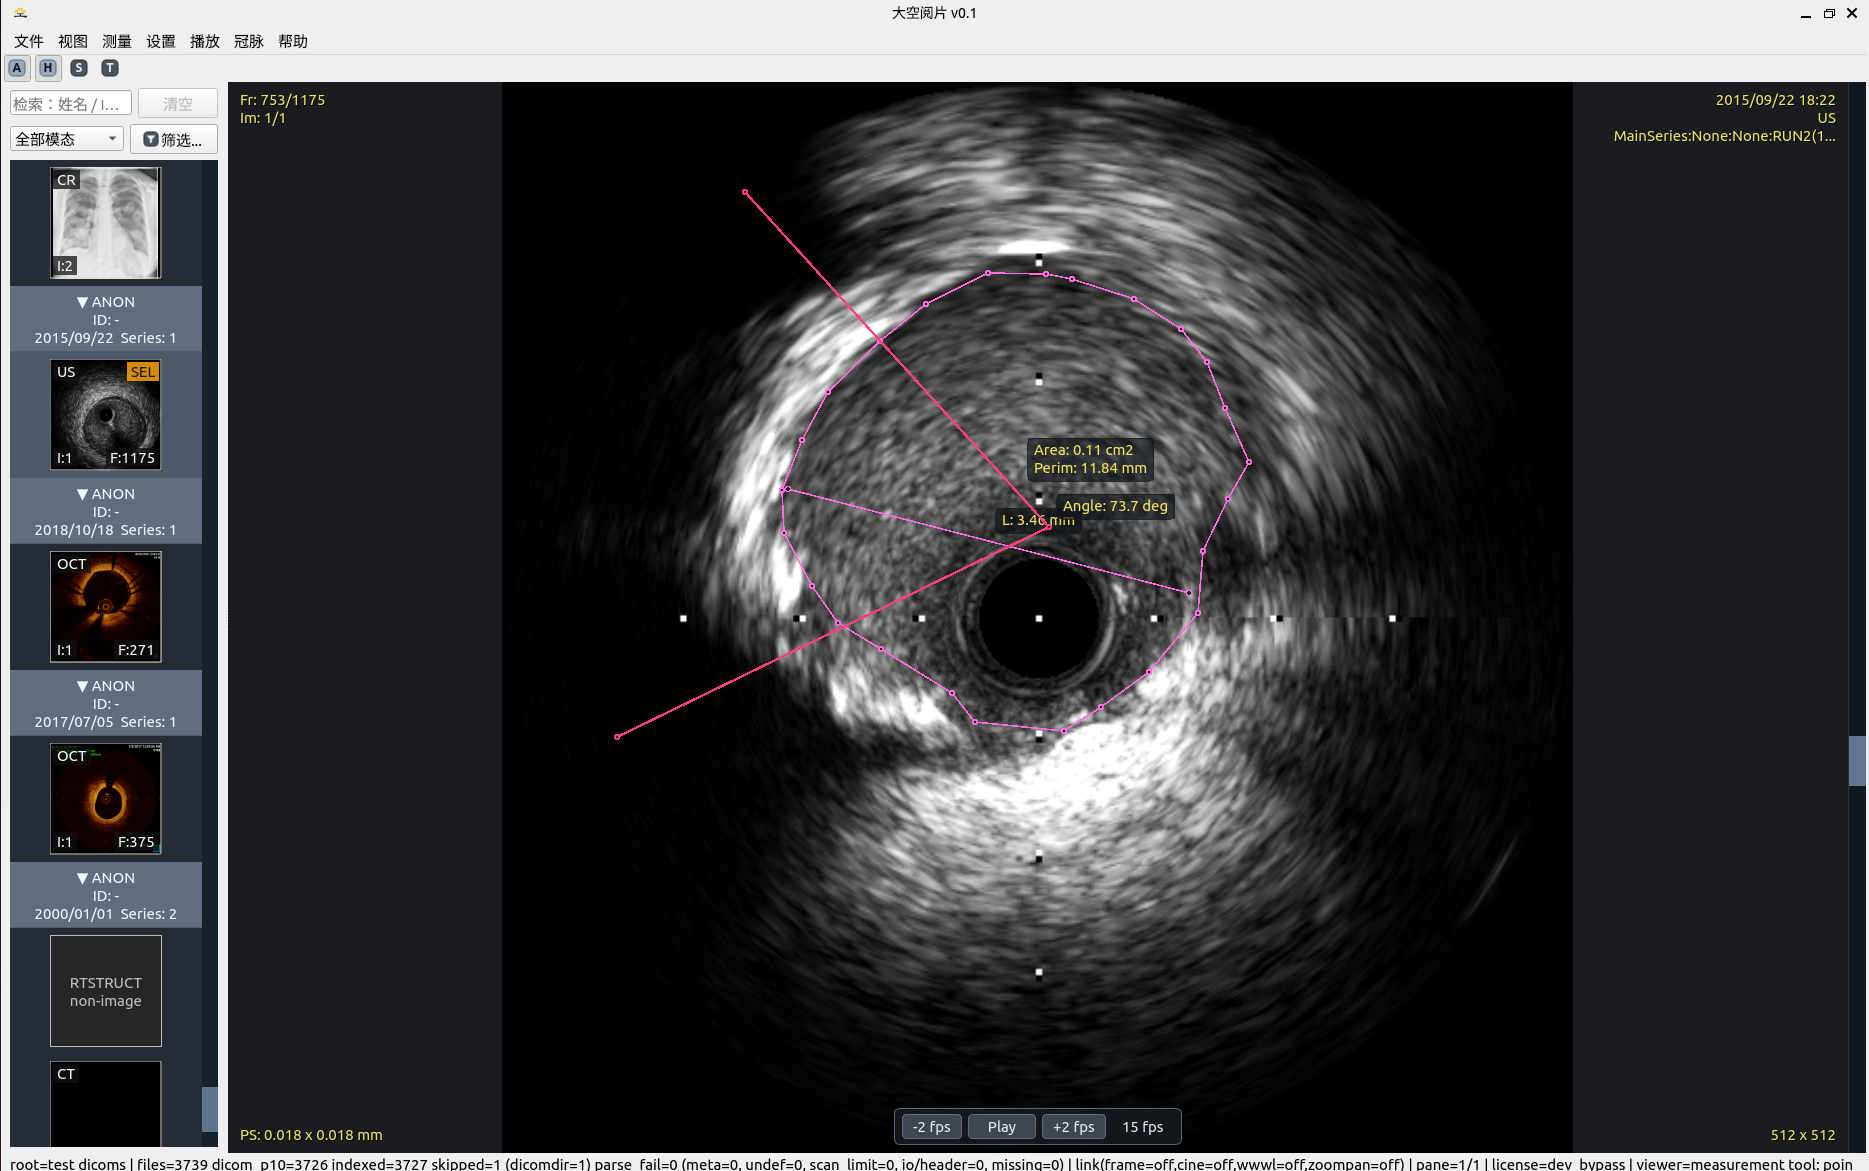

6. 腔内影像长轴重建(OCT/IVUS)

围绕临床 pullback 场景,提供“截面-长轴-测量”联动工作区。

• 截面旋转切割轴与长轴实时联动重采样。

• 支持序列定位回跳,便于分支口、病变段快速对照。

• 自动回撤模式下支持 mm 长度测量(帧率 + 回撤速度参数)。

腔内影像长轴重建

截面旋转轴与长轴联动,支持长度测量